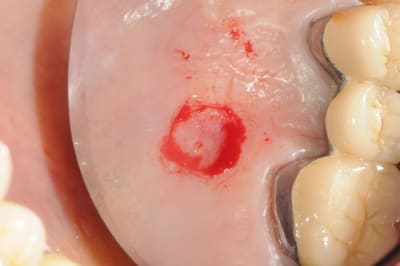

Le cas EII sur 12

positionnement de l'implant en ménageant un espace en vestibulaire qui st comblé avec de l'os synthétique car l'espace est important et il y a une perforation de la corticale vestibulaire en regard de l'apex de la dent.

pour recouvrir tout cela et gagner un peu de volume vestibulaire

un lambeau palatin pédiculé qui après une rotation va recouvrir l'implant et la greffe.